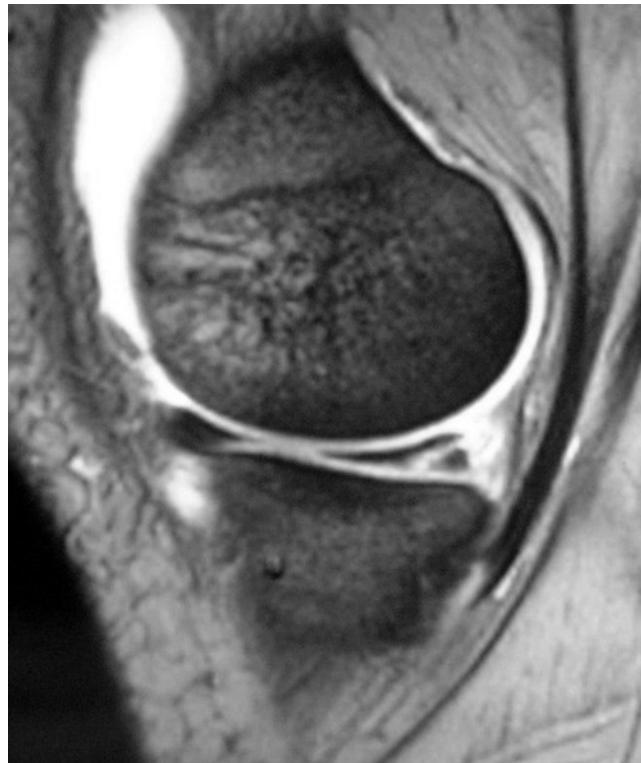

Examination of the knee

Knee Exam

https://www.youtube.com/watch?v=17ZKya9yR2Y

| Item | Procedure | Purpose/ Indication … | Attachment Links | Positive Finding/Interpretation |

| Meniscus: McMurry’s test OR Medial & Lateral joint tenderness Apley grinding test | Assess for meniscal tears | McMurry’s test: Apley grinding test: ![]() | Click, thud, or pain during knee flexion, extension, and rotation during McMurray’s; pain during compression and rotation during Apley’s. | |